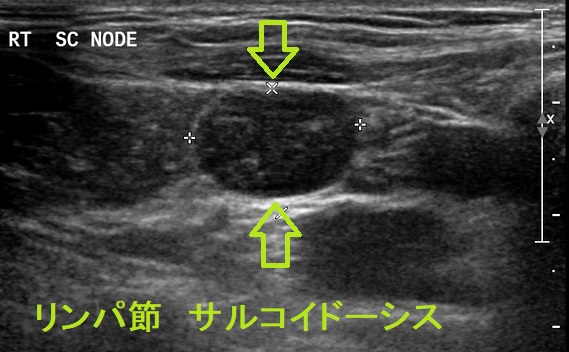

甲状腺乳頭癌の合併率は1.8%[Chest. 2006 Aug;130(2):526-32.]。頚部サルコイドーシスがある場合、リンパ節転移との鑑別が必要になります[BMJ Case Rep. 2018 Jun 8;2018:bcr2017222194.]

サルコイドーシスは活性型ビタミンD3への変換促進で高カルシウム血症に。sIL2-Rも高値(甲状腺機能亢進症、悪性リンパ腫でも高値)。サルコイドーシスは細胞性免疫異常で橋本病・バセドウ病、甲状腺乳頭癌合併多い。ステロイド投与で橋本病・バセドウ病も改善。甲状腺サルコイドーシスの超音波エコー画像は甲状腺悪性リンパ腫に類似。穿刺細胞診で甲状腺乳頭癌と診断される場合も。頚部サルコイドーシスは甲状腺乳頭癌リンパ節転移との鑑別要。甲状腺癌の肺転移と肺サルコイドーシスの鑑別が必要な場合ある。眼サルコイドーシスは甲状腺眼症/バセドウ病眼症類似症状。